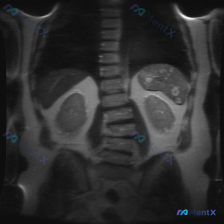

脾脏多发“靶征/牛眼征”结节:感染还是转移?影像细节背后的真相

整理了一份最近看到的腹部MRI病例,影像征象非常典型,感觉鉴别思路很有参考价值,分享出来和大家一起梳理下。

影像基础信息

- 序列:腹部MRI T2加权冠状位

- 主要展示:上腹部(肝、脾、双肾、脊柱、腹膜后)

关键影像表现

- 肝脏:轮廓尚平滑,实质信号基本均匀,未见明确占位。

- 脾脏:形态正常,但脾实质内可见多个散在、圆形/类圆形的异常信号灶。

- 信号特点:中心呈稍低信号,周围环绕高信号影,呈“靶征”或“牛眼征”样改变。

- 病灶边界相对清晰,大小不等。

- 双肾:皮髓质分界清,集合系统无扩张,未见明确占位。

- 其他:腹腔无明显积液,腹膜后大血管走行可,脊柱骨髓信号大致均匀。